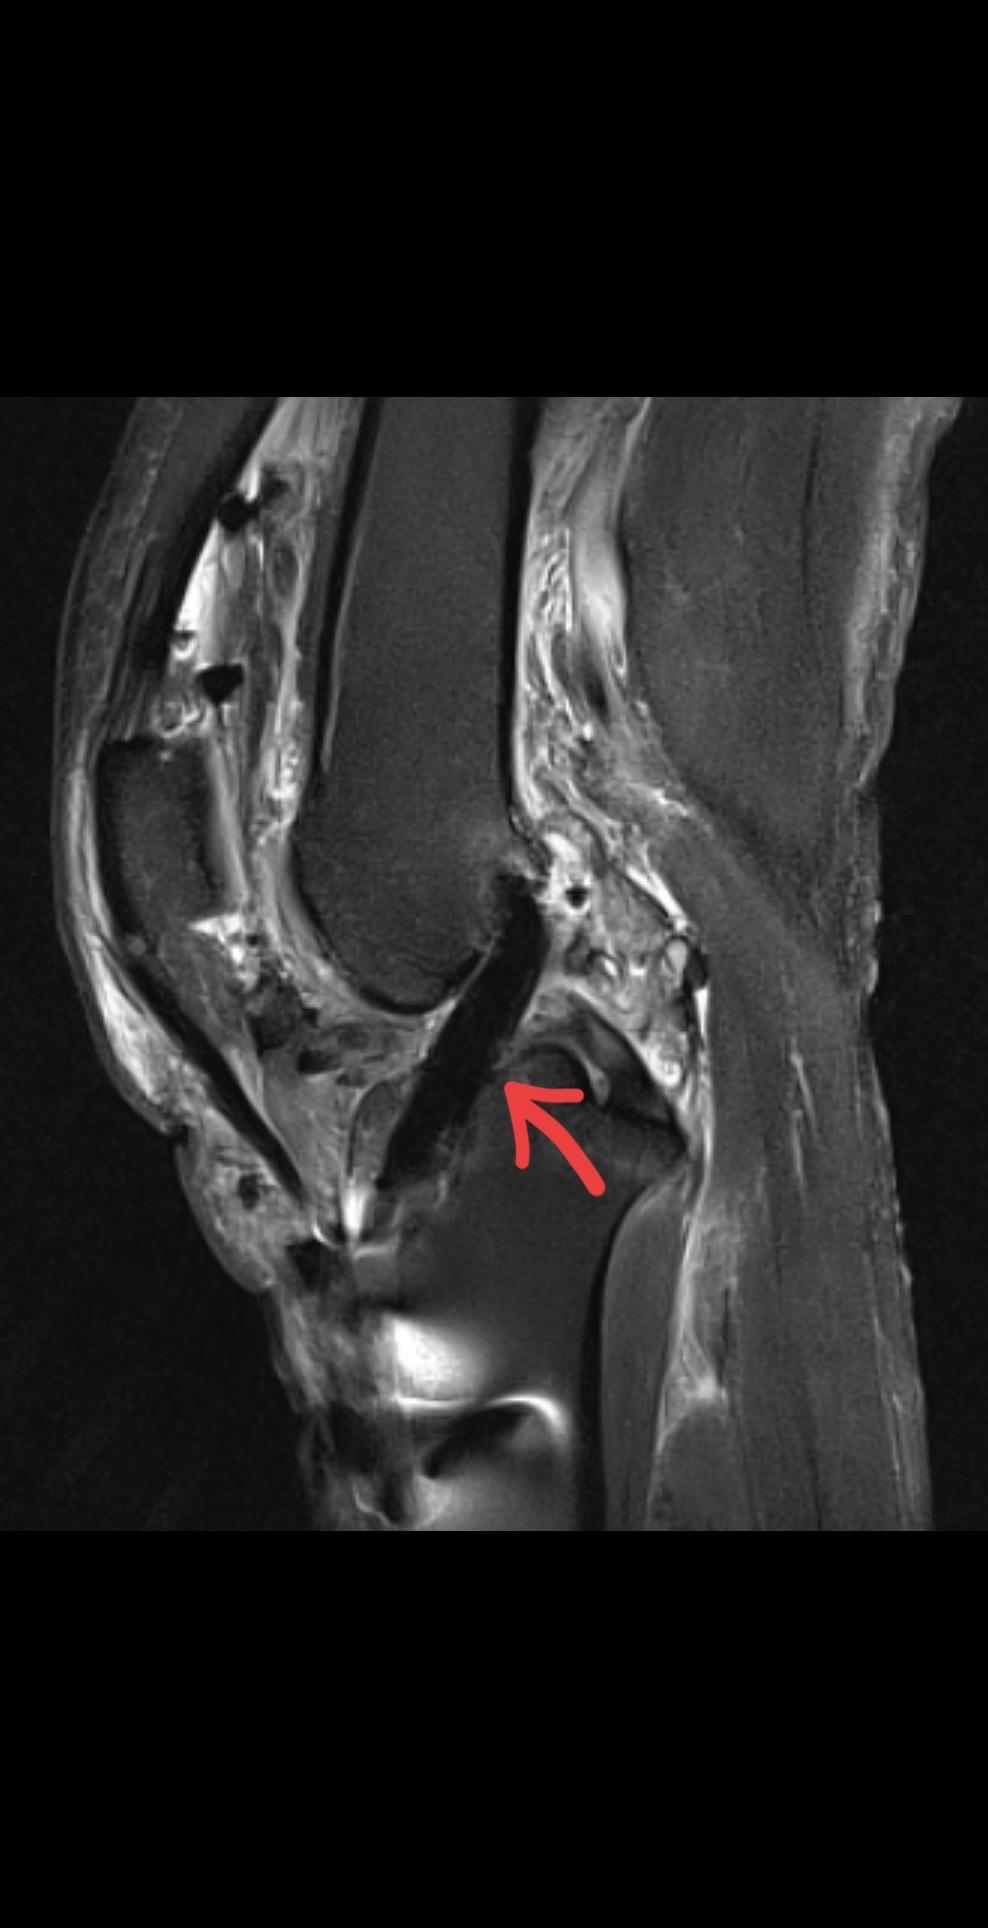

前交叉韧带重建术后影像评估。